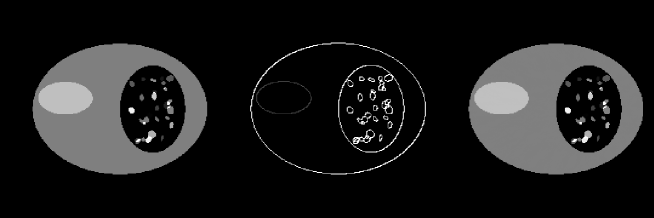

IV.1 Violation of gradient sparseness

In many applications the gradient images may be sparse only in an approximate sense. Even though it is a good approximation to assume that images will be constant over many regions, there will also be situations in which the images will have some level of variation within the regions. An important question is whether or not a low amplitude violation of gradient sparseness leads to only small deviations in images reconstructed by use of the TV algorithm. We investigate this issue by repeating the few-view and bad-bin studies described in Secs. III.1 and III.3, but adding a wavy background to the Shepp-Logan phantom.

Using the Shepp-Logan phantom with a wavy background in Fig. 11, we generated projection data at 20 views specified by Eq. (19). The amplitude of the wavy background is 1% of the gray matter attenuation coefficient. Any negative values in the phantom are thresholded to zero, so as to allow the applicability of the EM algorithm. With the wavy background the number of non-zero pixels in the gradient image jumps to 51,958 , but the majority of these non-zero values are small compared to the gradients at the boundaries of the different tissues. As was the case with the previous few-view study, the number of measurements is 10,240, which is less than twice the number of non-zero pixels in the gradient image, violating the sparseness condition.

In Fig. 11, we show the images reconstructed by use of the TV, EM, and ART algorithms from the 20-view data. The iteration numbers for obtaining these results were 200, 1000, and 500 for the TV, EM, and ART algorithms, respectively. The images in Fig. 11 indicate that the TV reconstruction is visually almost indistinguishable from the true image and that the EM and ART algorithms have difficulty with this data set. Upon further inspection of the image profiles, it can be seen that the TV algorithm does not yield an exact reconstruction. The small violation, however, of the gradient image sparseness does not appear to lead to large errors in the reconstructed image. We point out once again that this example does not constitute a mathematical proof, but it is suggestive of the conclusion that small violations in the gradient sparseness yields only small errors in the reconstructed image.

We also reexamined image reconstruction from data containing bad-bins of Sec. III.3 with the low amplitude wavy background added to the original image. In this case, the number of projection data is 58,430, which is not twice the number of non-zero pixels in the image but it is a comparable number. We display in Fig. 12 images reconstructed by use of the TV, EM, and ART algorithms. It can be observed that the TV image is visually indistinguishable from the true image. We also note that, as before, the ART and EM reconstructions are close to the original image in this case. The number of iterations for the TV algorithm is 100, which is much less than the 10,000 iterations used for both EM and ART algorithms.